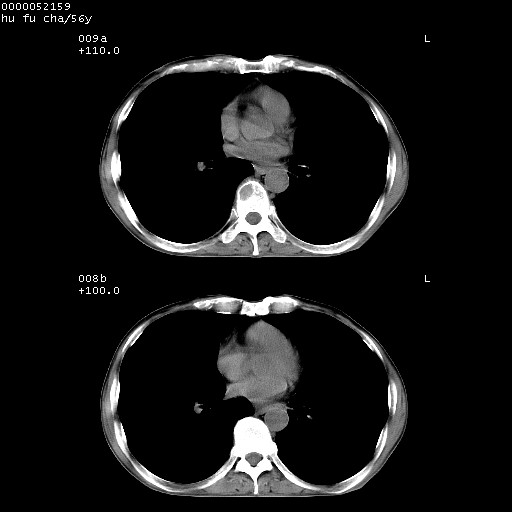

以下是引用zsl6918在2008-8-25 22:47:00的发言:[br]胸骨,胸椎及肋骨均可见多发转移表现,肝内低密度结节不除外转移。原发灶可能在右肺。双侧可见支扩表现。